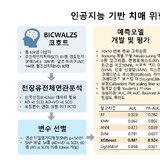

알츠하이머 치매 위험 조기 예측 길 열리나...인공지능 기반 예측모델, 임상적 활용 가능성 확인

- 10 알츠하이머 치매 위험 조기 예측 길 열리나...인공지능 기반 예측모델, 임상적 활용 가능성 확인